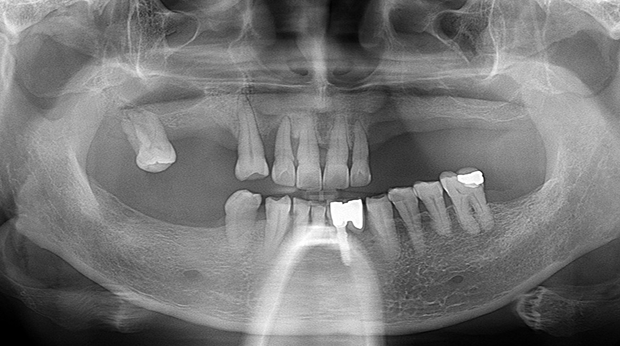

의식하진정법(수면마취)/임플란트

고난도 수술 진료

임플란트와 사랑니 발치는 외과적 시술로 잇몸을 절개하는 외과적 시술은

짧으면 짧을 수록 시술 후 붓기와 통증이 최소화됩니다.

치과의사 경력 14년차 구강외과 전문의가 빠르고 안전하게, 아프지 않게 수술해 드립니다.

치과경력 14년차 구강외과 전문의

연세대학교 치과대학 구강외과 임상 조교수